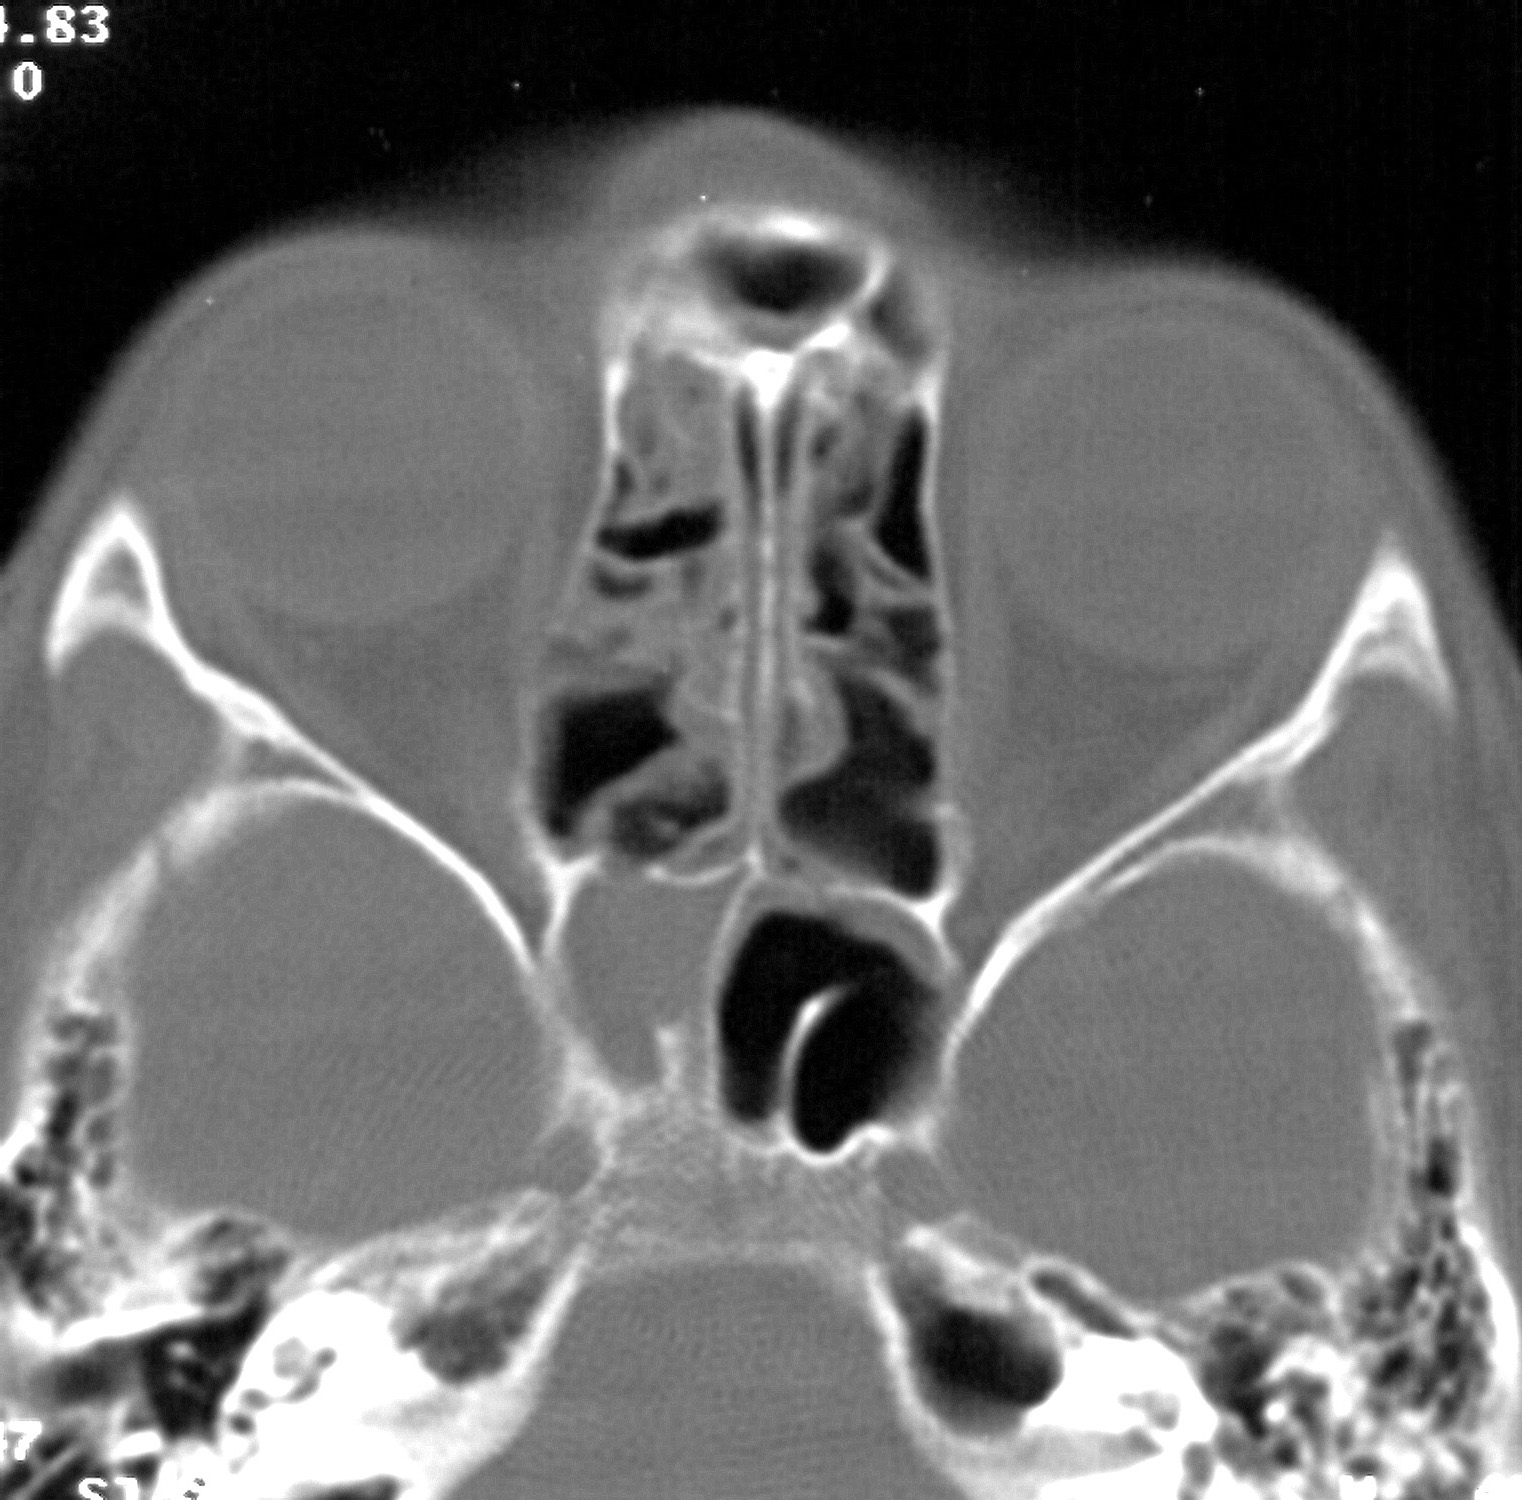

КТ-снимки хронического этмоидита: подробная визуализация